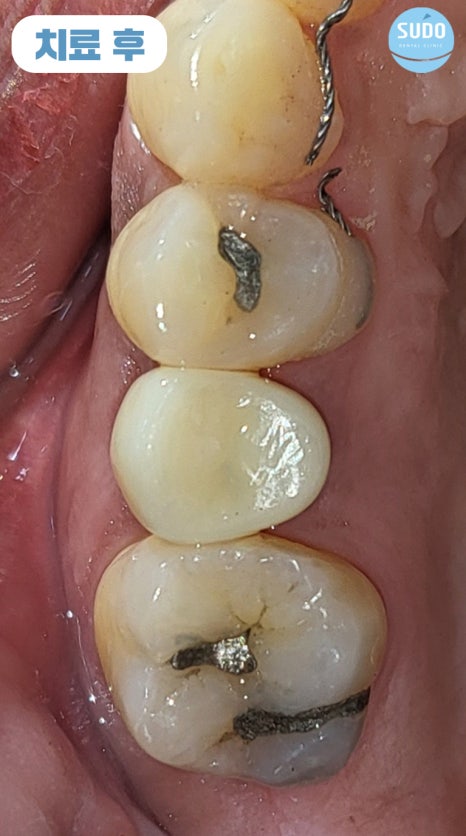

임플란트를 식립한 후 11월에 다시 한국을 방문하셨는데, 시간이 제한적이어서 며칠밖에 계시지 못하는 상황이라 부산영도임플란트의 상태를 확인한 후 맞춤형 지대주와 임시치아를 제작하여 장착한 후 다시 출국하셨습니다.

맞춤형 지대주는 개개인의 잇몸 형태에 맞게 정밀하게 제작되므로, 기성품과는 다르게 사용자 편의성과 최종 보철물의 안정성이 높아 파절 위험이 적습니다. 올바른 구강 위생 관리가 이루어진다면 반영구적으로 사용 가능합니다.

외국에 거주 중이신 분이라 전체적인 치료 기간은 길어졌지만 큰 어려움 없이 마무리되었고, 5개월 정도 임시치아 상태로 편하게 사용하신 후 최근 다시 한국으로 돌아오셔서 최종 보철물까지 마무리할 수 있었습니다.